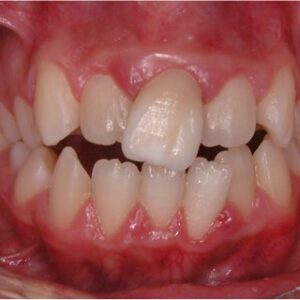

غالبًا ما تكون هذه الحالة مصحوبة بالعضّة المعكوسة (Crossbite) عند الأطفال، أي أن الأسنان الخلفية للفك العلوي تنمو داخل الفك السفلي، كما لو أن قطع أحجية لم توضع في مكانها الصحيح.

- ازدحام الأسنان: الأسنان تتراكم فوق بعضها بسبب قلة المساحة

- عضّة معكوسة (كراس بايت): الأسنان الخلفية للفك العلوي تنتقل إلى الفك السفلي

عند مناقشة علاج ضيق الفك العلوي، لا نفكر فقط في استعادة الجمال، بل في غير ذلك قد يواجه الشخص مجموعة من المشاكل الوظيفية. على سبيل المثال، من الناحية السنية، العضّة المعكوسة وضيق الفك العلوي يؤديان إلى تآكل غير متساوٍ للأسنان وصعوبة في المضغ، وبالتالي اضطراب الهضم. علاج ازدحام الأسنان غالبًا يحتاج إلى التوسيع الأولي، لذلك تقويم الأسنان وحده لا يكفي.